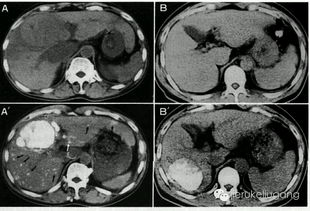

肝转移癌-肠癌术后三年肝上发现占位,肝胆外科评估后二次手术切

引言:当转移的阴影再次降临 对于许多结直肠癌患者而言,成功完成初次根治性手术,意味着赢得了一场至关重要的战役。术后的康复之路并非总是一帆风顺。据统计,高达50%至70%的结直肠癌患者在术后会出现肝转移,其中一部分甚至在术后三年内,于定期复查中发现肝脏出现了新的“占位性病变”。这无疑是给患者和家庭投下的一片沉重阴影。当影像报告上出现“肝内多发占位,考虑转移瘤可...